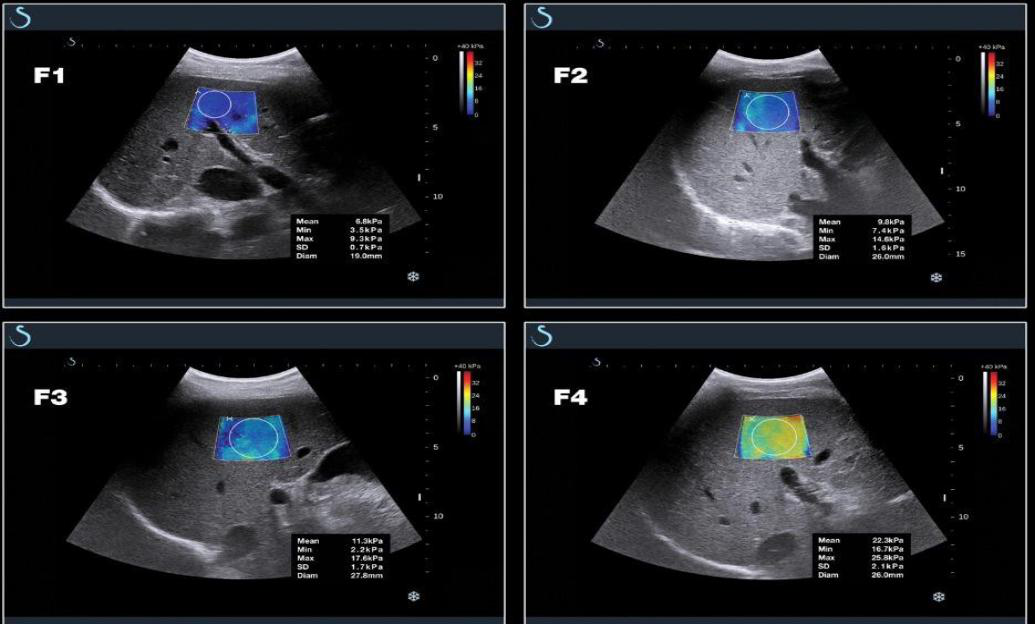

▲肝纤维化 F1-F4 期的 E 成像图像和测量数据:随肝纤维化程度的不断加重,E 成像 颜色由深蓝-亮蓝-绿- 黄,杨氏模量值也不断升高。